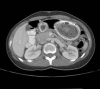

Figure 1.

Axial computed tomography demonstrating bezoar obstructing entire lumen of stomach.